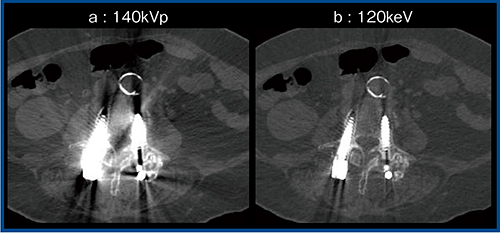

一方,高keV(高エネルギー)画像は,ブルーミングアーチファクトや金属アーチファクト低減に有用である(図3)。140kVpで撮像した画像(図3 a)と比較して,高keV(120keV)画像(図3 b)では金属スクリューからのアーチファクトが低減され,脊柱管内の観察も容易である。

図3 高keV画像による金属アーチファクトの低減1)